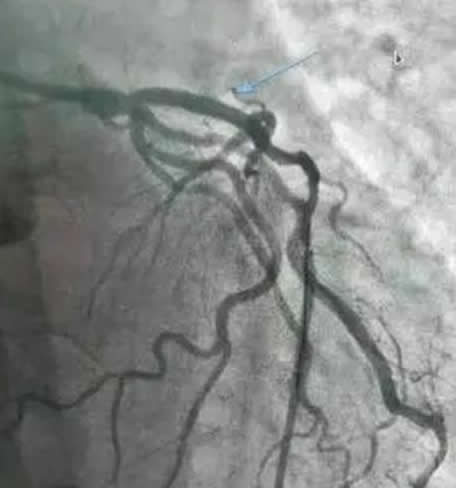

王某诉医学科学院阜外医院(西城区)冠脉造影出现夹层并发症后未履行告知义务,术后并发心梗未请会诊,没有积极履行诊疗职责,最终患者心脏破裂去世医疗纠纷赔偿案